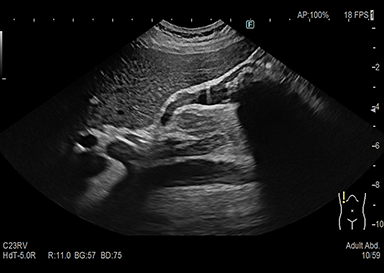

超音波検査とは

頸部(動静脈・甲状腺)、心臓、腹部(肝臓・胆のう・膵臓・脾臓・腎臓・膀胱・腹部大動脈等)、下肢(動脈・静脈)等が観察できる検査です。

高齢者でも無理なく行えます。病変の経過観察、早期発見としたスクリーニング検査などが行えます。